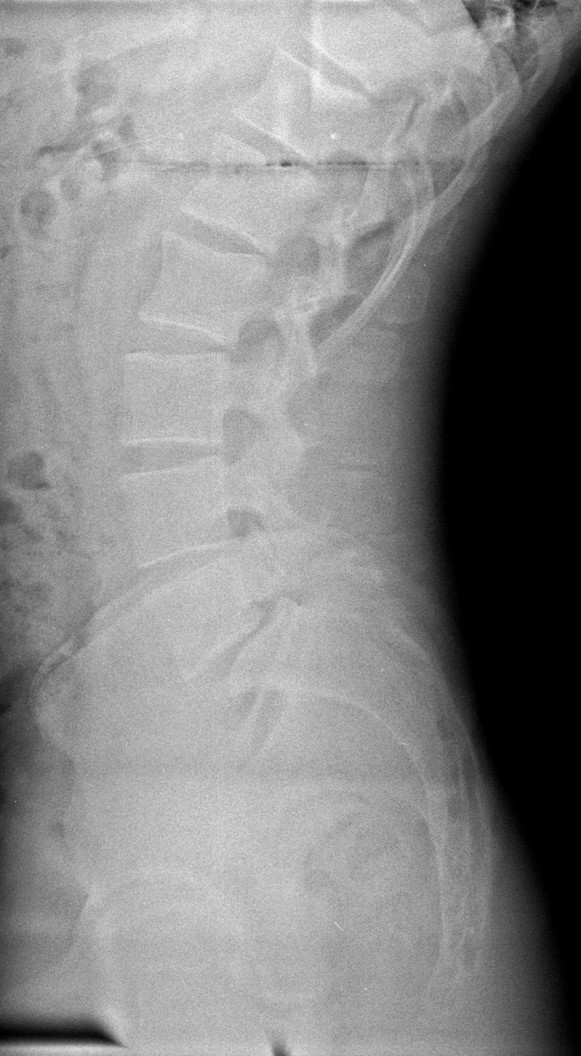

34 Yaşında Erkek Hasta

Low back pain

ODİ: %16

RM: 5/24

Ameliyat Öncesi